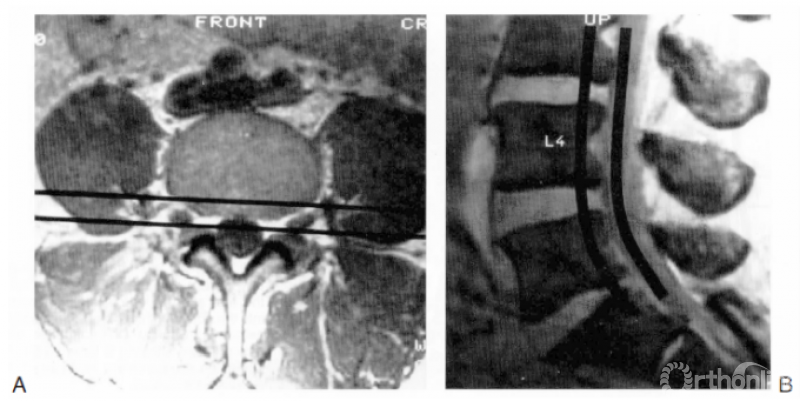

为了便于确定椎管内病变的具体位置,我们建议对每一脊柱节段进行3层解剖分区(3个楼层)(图18.6)。这一概念有助于脊柱外科医生在脑海中勾勒出病变在椎间盘-椎体柱与神经柱间的确切定位(图18.7)。

图18.6 解剖节段的3层分区法。第1层为椎间盘水平,第2层为椎间孔水平,第3层为椎弓根水平

图18.7 应用3层分区法确定病变在前方椎间盘/椎体柱与后方硬膜囊之间的位置。A:横截面图像,两条黑线之间为前方椎间盘/椎体柱与后方硬膜囊的界面;B:矢状位

以椎弓根下缘作为虚拟的分割线,每个解剖节段如同一幢楼房一样可分为3层(这个概念非常清楚易懂)。接下来对各层进行判读,这样外科医生可以很准确地定位病变在椎间盘/椎体柱与神经柱间的具体位置。图18.8-18.10所示为各层病变的举例。